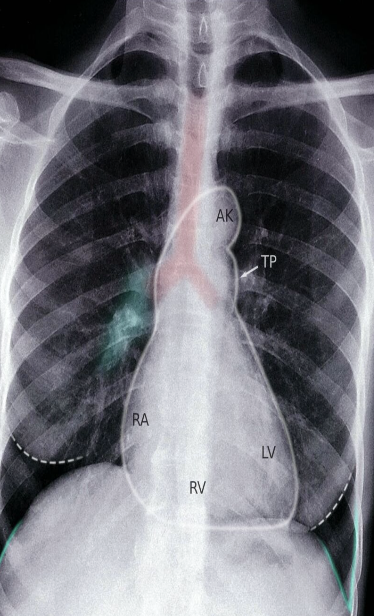

Heart : The cardiac silhouette (outlined in white).

Hilum : Pulmonary hila (example indicated by green overlay).

LV: left ventricle; RV: right ventricle; RA: right atrium; PT: pulmonary trunk (white arrow); AK: aortic knob; Trachea: red overlay, Breast shadow: white dotted outline